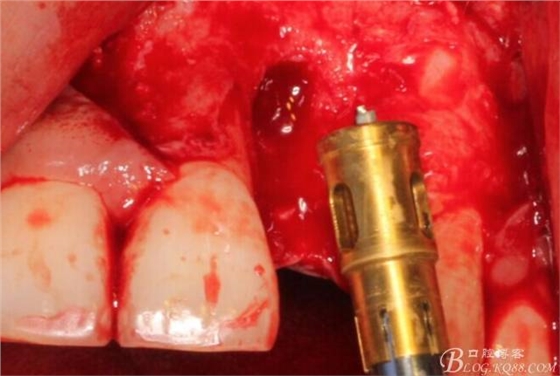

根方用取骨鉆取自體骨。

旋入一長兩短3顆鈦釘。